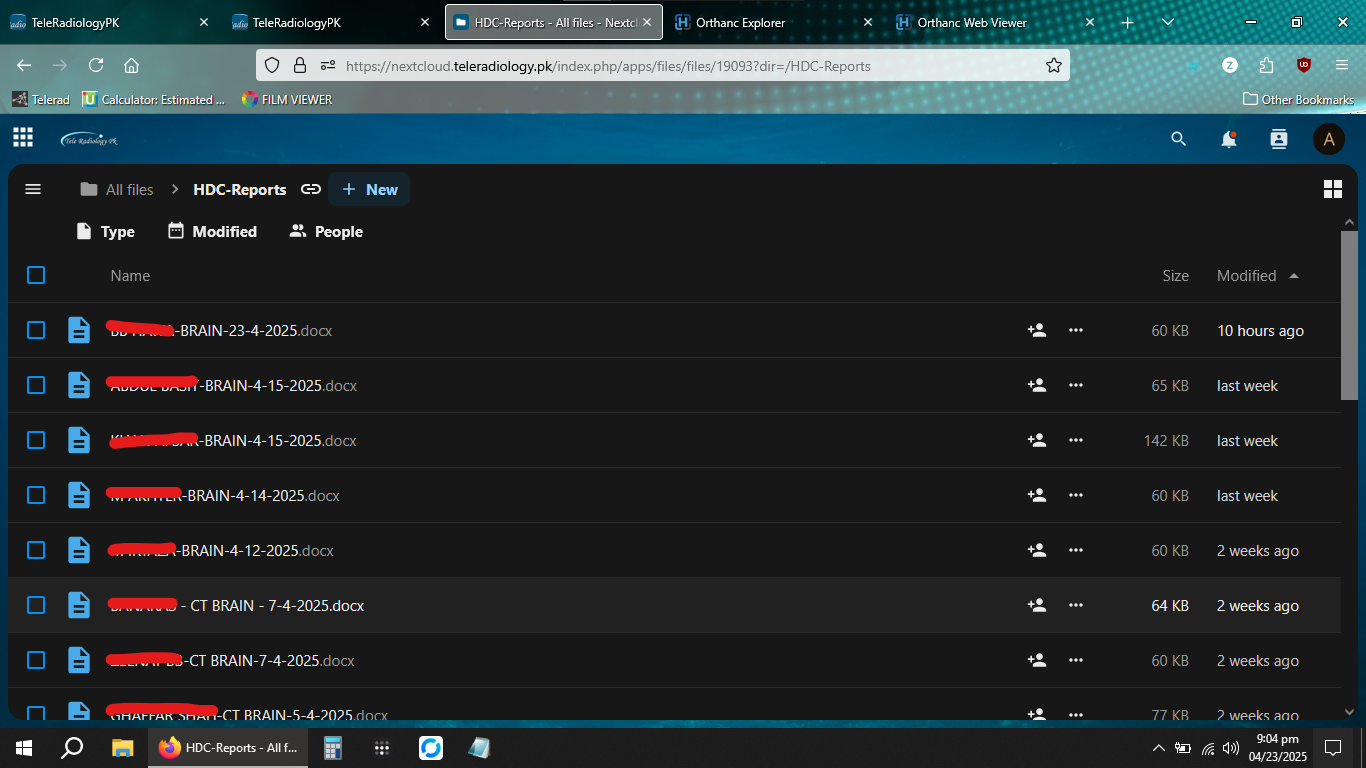

We provide guidance for implementation of our PACS server into respective Radiology modalities including MRI, CT, X-Rays and Ultrasound. For machines without activated DICOM nodes, studies can be sent to us via dedicated password protected links after retrieval from the machines.